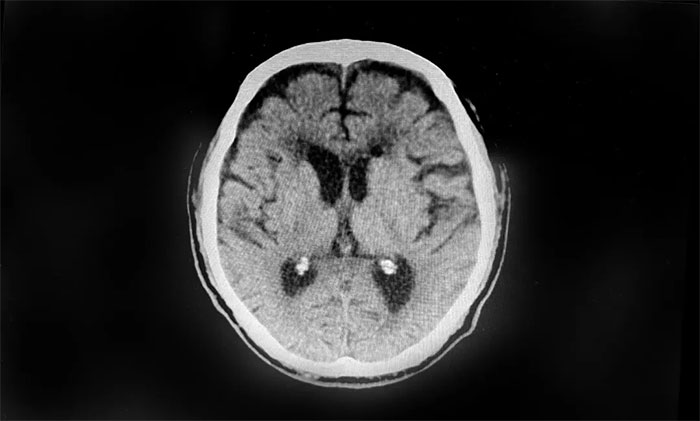

行顱腦CT檢查,患者雙側(cè)額顳枕頂部可見硬膜下積液血腫,雙側(cè)額葉受壓明顯,不排除積液血腫進一步加重。若不及時手術(shù)治療,病情可能進一步惡化,甚至可能危及生命。

▲ 患者雙側(cè)額頂部硬膜下積液血腫明顯